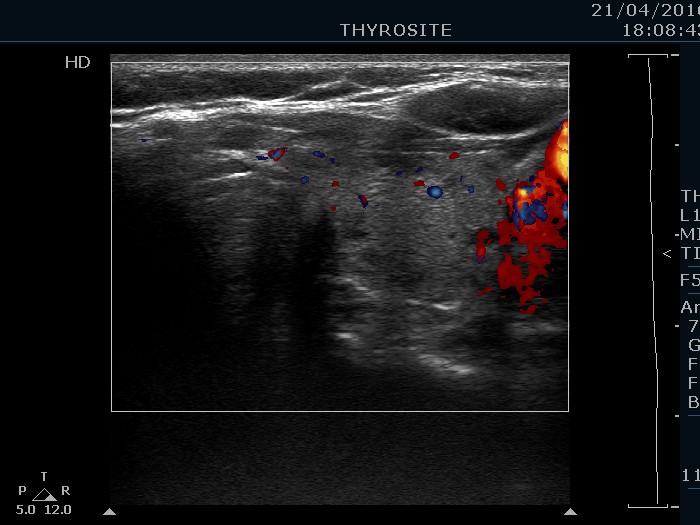

100 consecutive cases of papillary cancer - case 056 (ultrasonographic picture 8)

Left lobe, transverse scan, color Doppler mode.